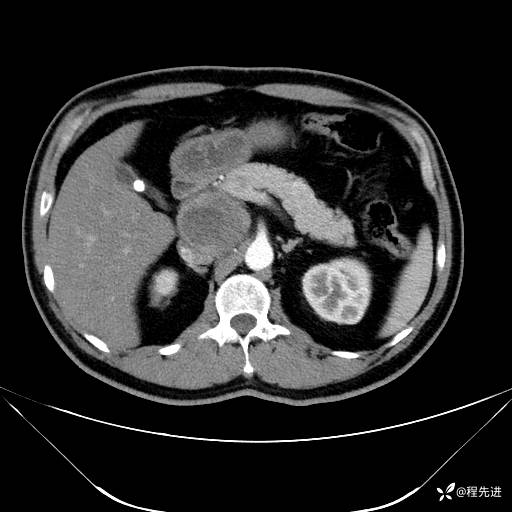

【腹盆】特别精彩病例|发现腹膜后肿物1月余

主诉:发现腹膜后肿物1月余

现病史:患者1月余前查体,行超声检查提示:后腹膜囊实性肿块;慢性胆囊炎伴胆囊内结石;无腹痛腹胀,不伴腹泻发热等;偶感腰背部酸痛。

实验室检查:乙肝表面抗原(+),乙肝e抗体(+),乙肝核心抗体(+)

肿标:(-)

CT平扫+增强: